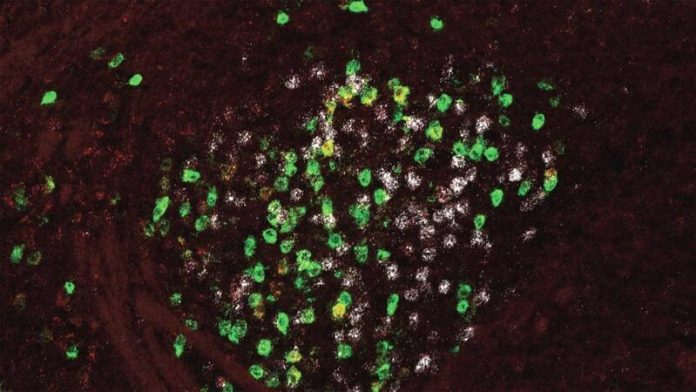

Muchos de sus estudios comienzan con la amígdala, una estructura en forma de almendra que se considera el centro del procesamiento del miedo en el cerebro. Si bien antes se pensaba que la amígdala se dedicaba exclusivamente a procesar el miedo, los investigadores ahora están ampliando su comprensión de su función.

Los investigadores se sorprendieron al descubrir que la amígdala se comunica con una parte del cerebro más conocida por su papel en el control del movimiento. La estructura, llamada globus pallidus, no se sabía que estaba involucrada en el procesamiento del miedo o la formación de la memoria.